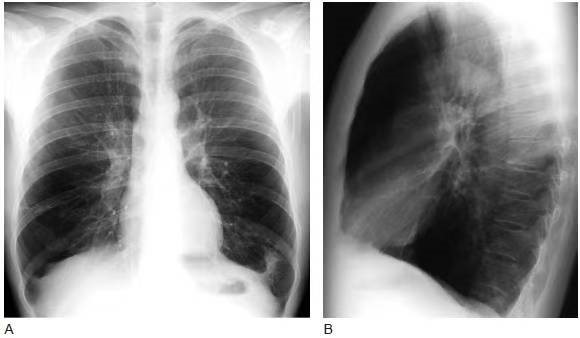

X线:轻度病变非常不敏感;晚期病变主要表现为肺膨胀过度和血管改变。

(1)肺膨胀过度的征象:1.肺野透光度升高;2.肺高增大;3.膈肌低位,膈肌变平;4.胸骨后间隙增宽。此外,还可有肋间隙增宽、纵隔向健侧移位等间接征象。

(2)血管改变:包括气肿区肺血管纹理变细、稀疏,非气肿区则代偿性的血管增粗、增多,为血流再分配表现。